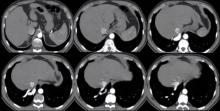

This video demonstrates a VATS resection of extralobar sequestration in an asymptomatic patient. A 40-year-old male patient was admitted for abnormal findings on his chest radiography. The authors suspected a sequestration, and performed CT-angiography in order to make a diagnosis. This revealed a feeding artery that was originating from the abdominal aorta, and a vein that was draining to the inferior vena cava. This video represents the VATS resection of the extralobar sequestration. The patient was discharged on the third postoperative day without any problem. The authors believe that VATS resection of an extralobar sequestration is feasible and safe.